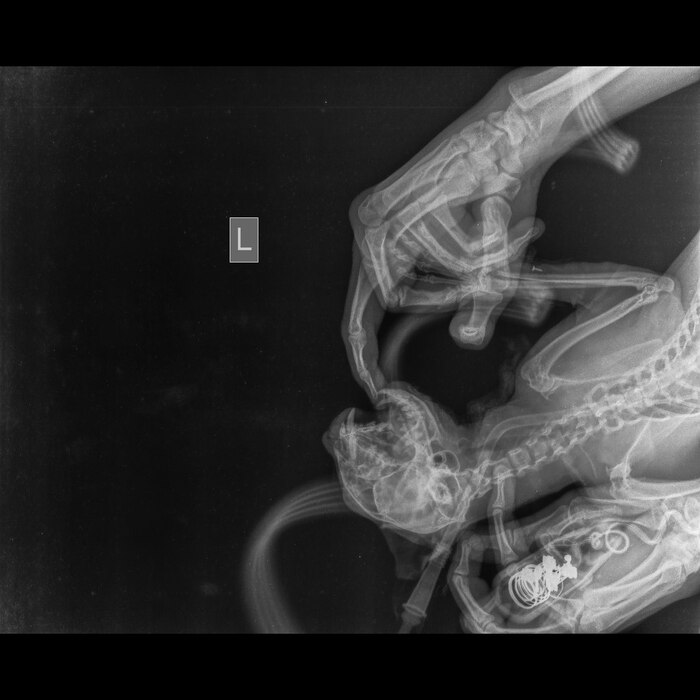

Пока кошка Милка от которой отказались ее же хозяева продолжает лежать у нас, сегодня был разговор со стоматологом.К сожалению стоматолог находится в другой клинике и не может приехать осмотреть животное, но он попросил сделать снимки записать видео, что бы предположить хотя бы какой диагноз у кошки.

После этих манипуляций был поставлен пока предварительный диагноз: Вывих височно- нижнечелюстного сустава?Перелом нижней челюсти по симфизу?

Прикладываю рентгены кошки